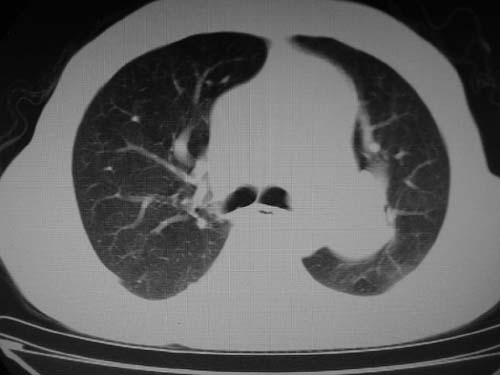

1)考虑左肺动脉瘤可能性大,建议增强。2)右肺上叶继发性肺结核。3)右侧胸膜增厚、钙化,左侧胸膜反应。

)考虑肺动脉扩张,右心室增大,主动脉弓段正常位弓后段明显变小(不会是动脉导客未闭吧,不知患者有何症状病史)0。2)右肺上叶继发性肺结核。3)右侧胸膜增厚、钙化,左侧胸膜反应。

结合患者年龄,不除外左下肺扩张性动脉瘤,建议胸透是否有扩张性博动,以便确诊。